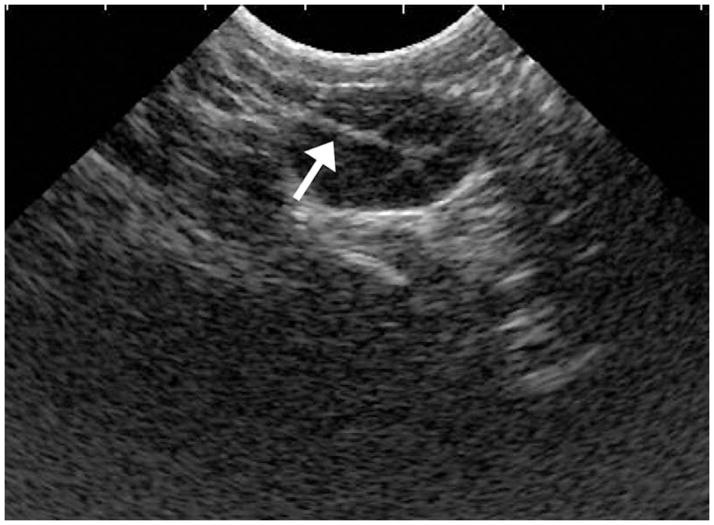

Figure 3.

Abdominal ultrasound image of rhesus monkey ovary during follicular aspiration. Arrow indicates the echogenic tip of aspiration needle.